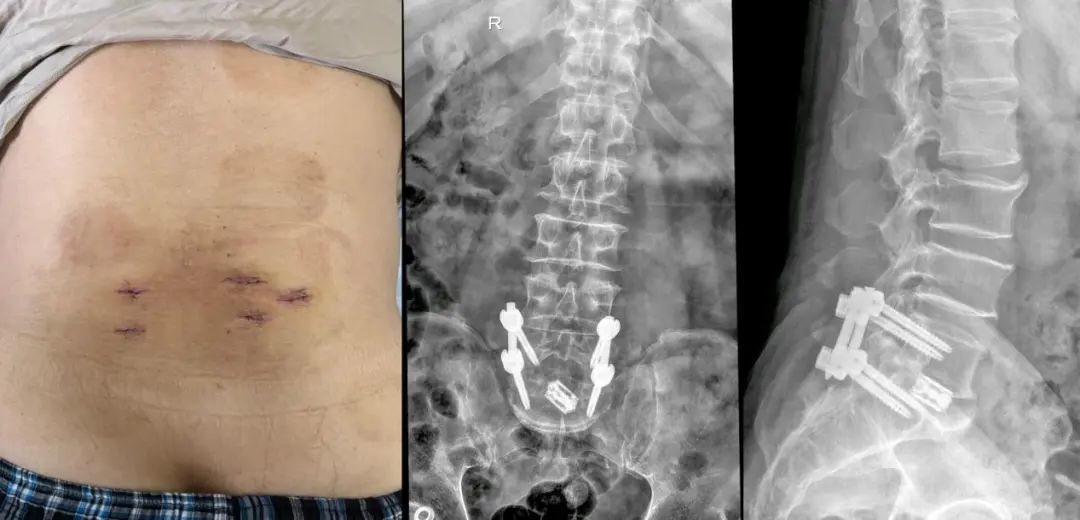

根据预定的手术方案,在麻醉科和手术室护理团队的配合下,手术团队通过5个不足2cm的经皮手术切口,便顺利完成了经皮通道下椎间融合、孔镜椎管减压及经皮固定。整个手术过程,出血量不超过50ml,并且术后无需放置引流管,实现了最大程度减少手术创伤的目的。

术后,杨大爷即刻就明显感觉到困扰他多年的腰腿痛症状竟然消失了。更令人振奋的是,术后第一天,他便能直起腰正常下地行走和活动了,这在传统的开放式手术中是难以想象的。杨大爷面对如此神奇的治疗效果,对胡勇主任、赖欧杰主任医师及救治团队都表示了由衷的感谢,直言六院又让他“挺直腰板”了。